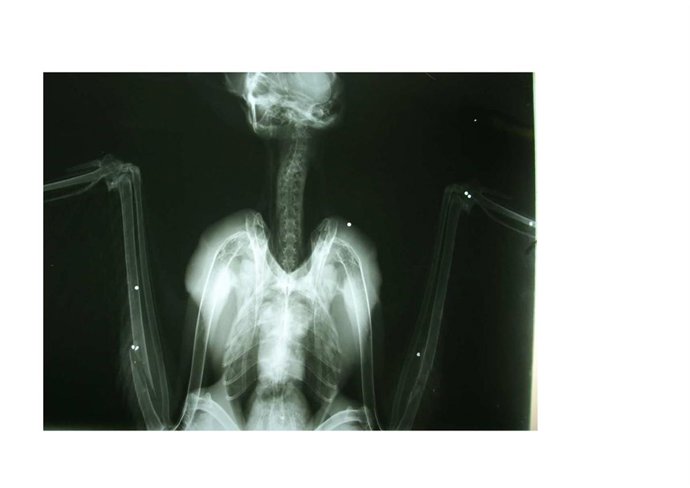

Radiografía de cernícalo con perdigonazos

Los agentes rurales de Tarragona recuperaron durante 2010 un total de 17 aves de diversas especies protegidas que resultaron heridas por arma de fuego, entre las que se encuentran búhos reales, águilas, gavilanes y cernícalos, ha informado este lunes la Consejería de Agricultura y Medio Natural de la Generalitat.

El pájaro, que se ha liberado en el bosque de La Marquesa, dentro del Espacio de Interés natural Tamarit-Punta de La Mora (Tarragona), había sido herido por diversos impactos de perdigón y presentaba diversas fracturas.